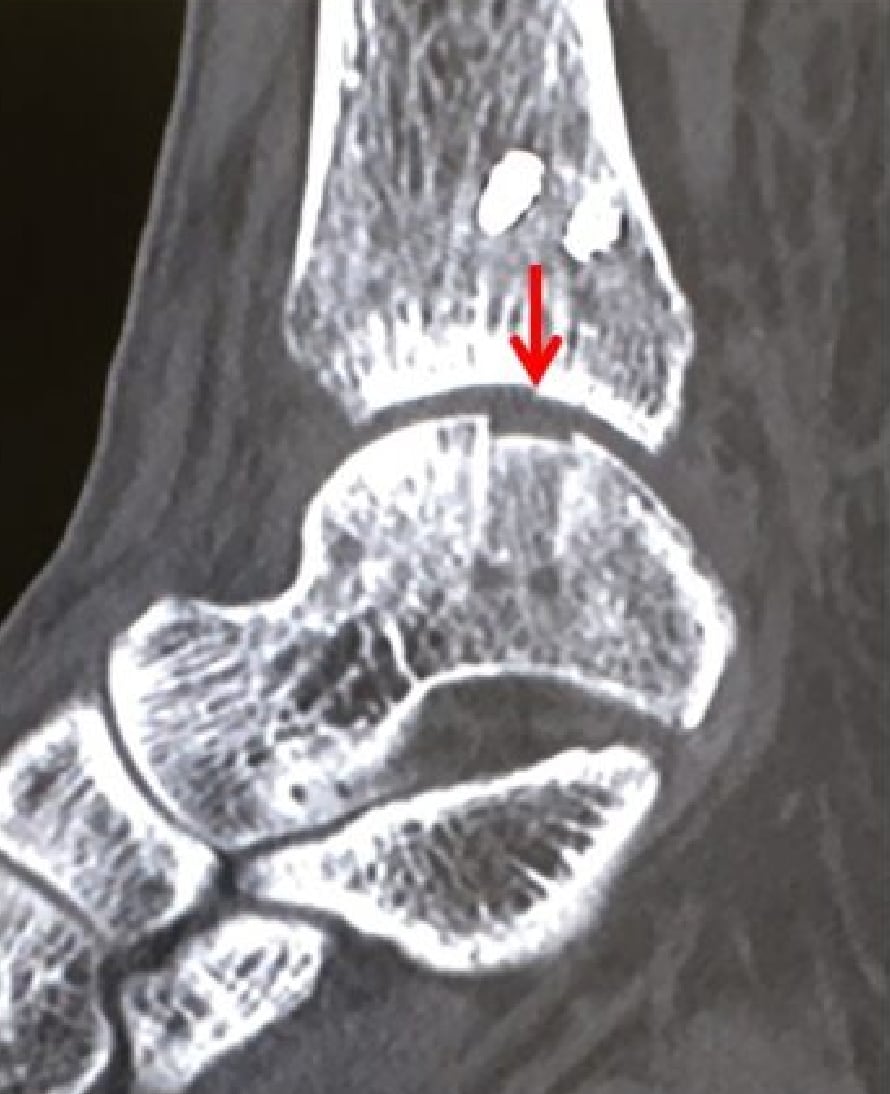

骨軟骨柱移植後

術後6ヶ月経過CT 1

術後6ヶ月経過CT 2

骨軟骨柱移植術後CT